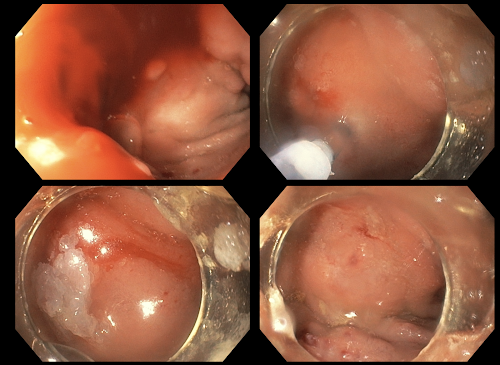

Mujer de 54 años, con cáncer de páncreas estado clínico IV, trombosis de vena cava, con sangrados digestivos recurrentes masivos de dos meses de evolución. En la presente endoscopía se encuentra en duodeno dos várices seudotumorales, una post pilórica y otra en cara anterior, ambas con "signo de pezón blanco" o "tapón fibrinoplaquetario" (fotos 1-4).